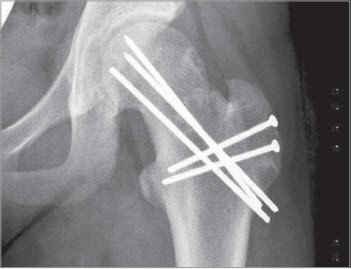

3 Postoperatives Bild in der AP-Projektion nach offener Epiphysenreposition nach Trochanter flip-Ostoetomie

nach offener Reposition